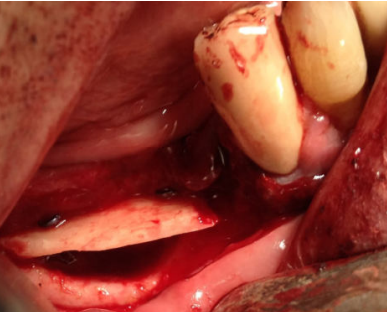

El injerto en bloque obtenido se dividió con la ayuda de un disco de corte en dos láminas corticales de 1,5 mm (Figura 4). Seguidamente, se fijó una de las láminas en la parte coronal del defecto óseo, creando un espacio virtual en altura de aproximadamente 6 mm que se rellenó con las partículas de hueso autógeno obtenidas (Figura 5). La lámina remanente se posicionó y fijó conformando la pared vestibular del defecto (Figura 6). La sutura se llevó a cabo mediante puntos de colchonero, favoreciendo así la cicatrización, y se utilizó monofilamento de 5/0. El CBCT postquirúrgico de control mostró una correcta reconstrucción tridimensional del defecto y el postoperatorio cursó con normalidad, sin signos infecciosos ni dehiscencias de la herida y sin alteraciones sensitivas (Figura 7).

Por este motivo, en el presente caso clínico, el fragmento óseo obtenido se divide en dos láminas corticales de poco grosor que encofran el defecto óseo, para poder rellenarlo con partículas óseas obtenidas con rascadores óseos del área donante. De esta manera, se cumplen los principios de un injerto ideal, que debería tener una fina lámina cortical y abundante hueso medular, evitando el inconveniente de los injertos por aposición9,25.